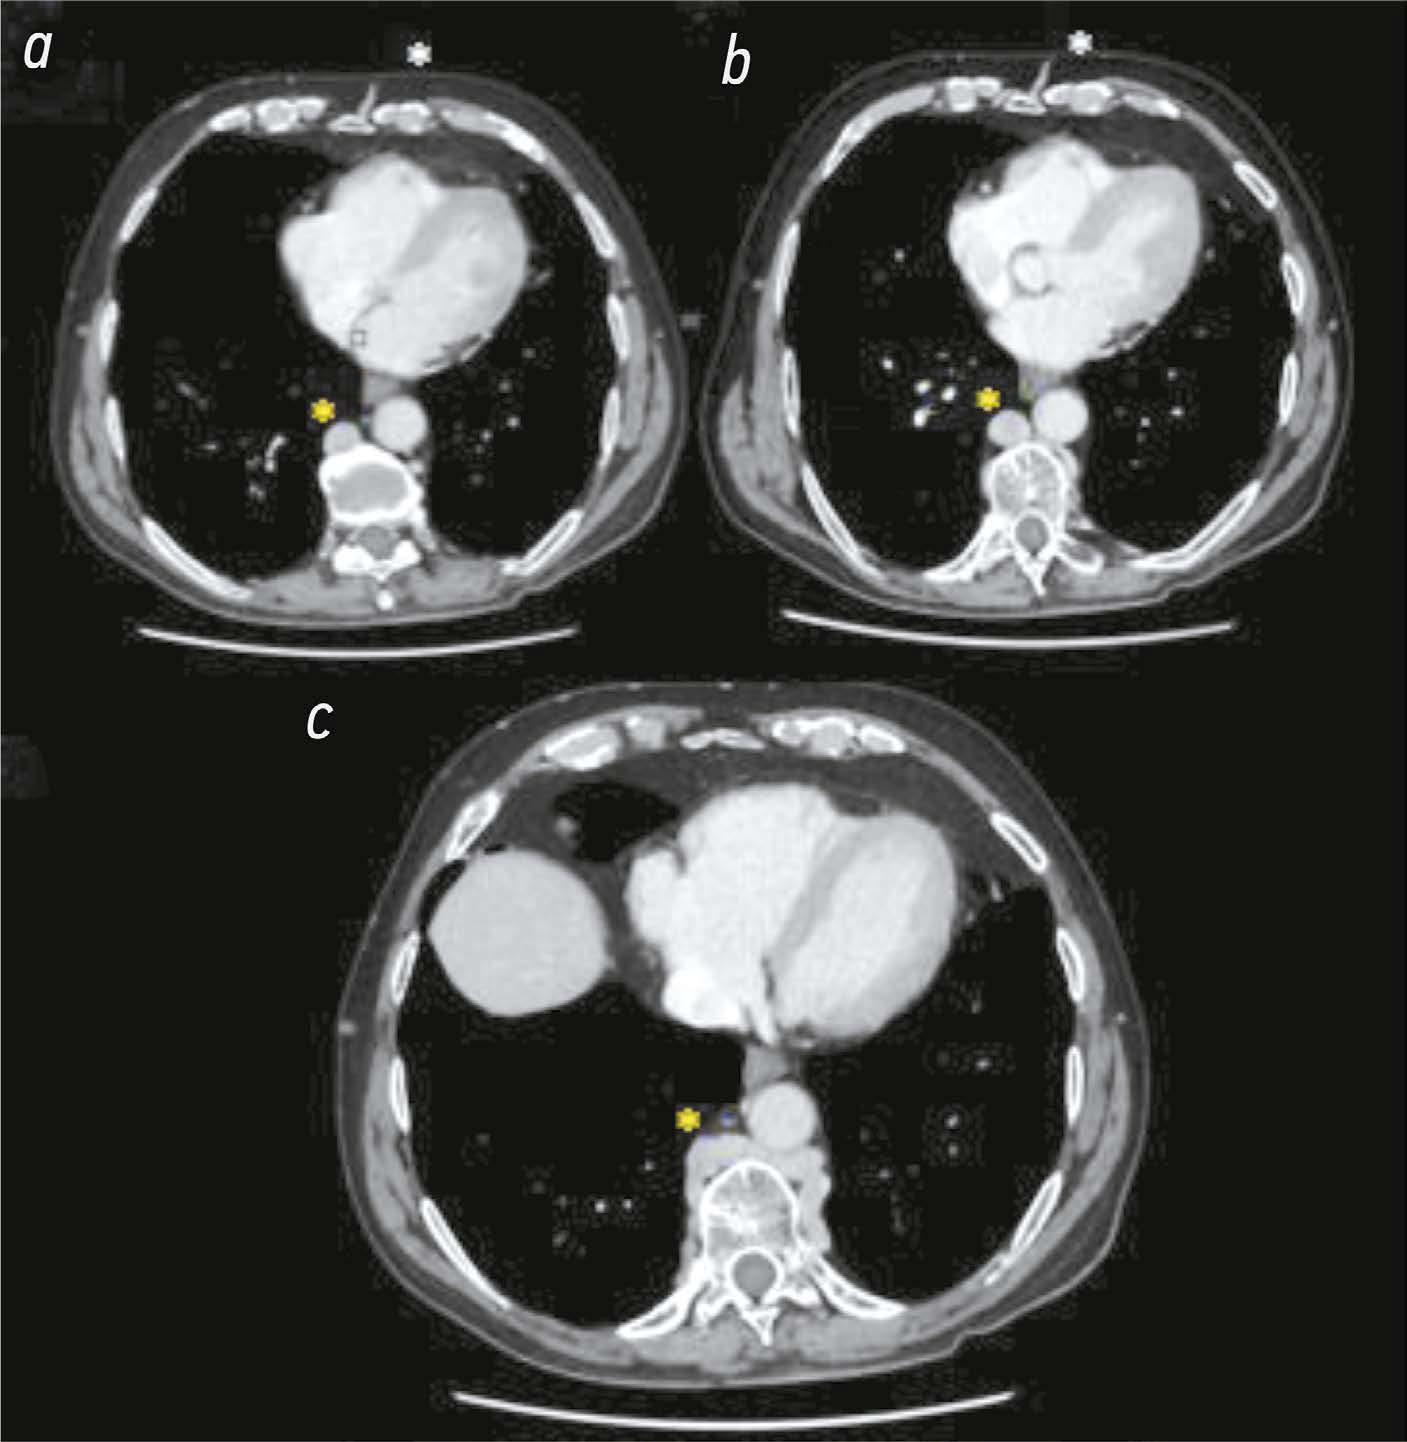

Abstract

The differential diagnosis of an echocardiographically detected intracardiac mass in the mitral annulus can be challenging and usually requires a multimodal approach. This type of lesion is very often associated with subvalvular calcification of the mitral valve. The rare, caseous, variant is the most difficult to diagnose. This case series highlights the clinical significance of computed tomography in detecting and characterizing subvalvular mitral annular calcification when other modalities, particularly echocardiography, are inconclusive. The aim of this article was to raise awareness among specialists of the classic signs of caseous subvalvular calcification of the mitral annulus when visualized with different modalities. Special attention is also given to providing a differential diagnostic series that identifies features that differentiate subvalvular calcification of the mitral annulus from other conditions at this site. Healthcare professionals need to be aware of these mitral valve lesions in order to predict possible associated complications and plan a treatment strategy that may help avoid unnecessary surgical procedures in some cases.

893-901